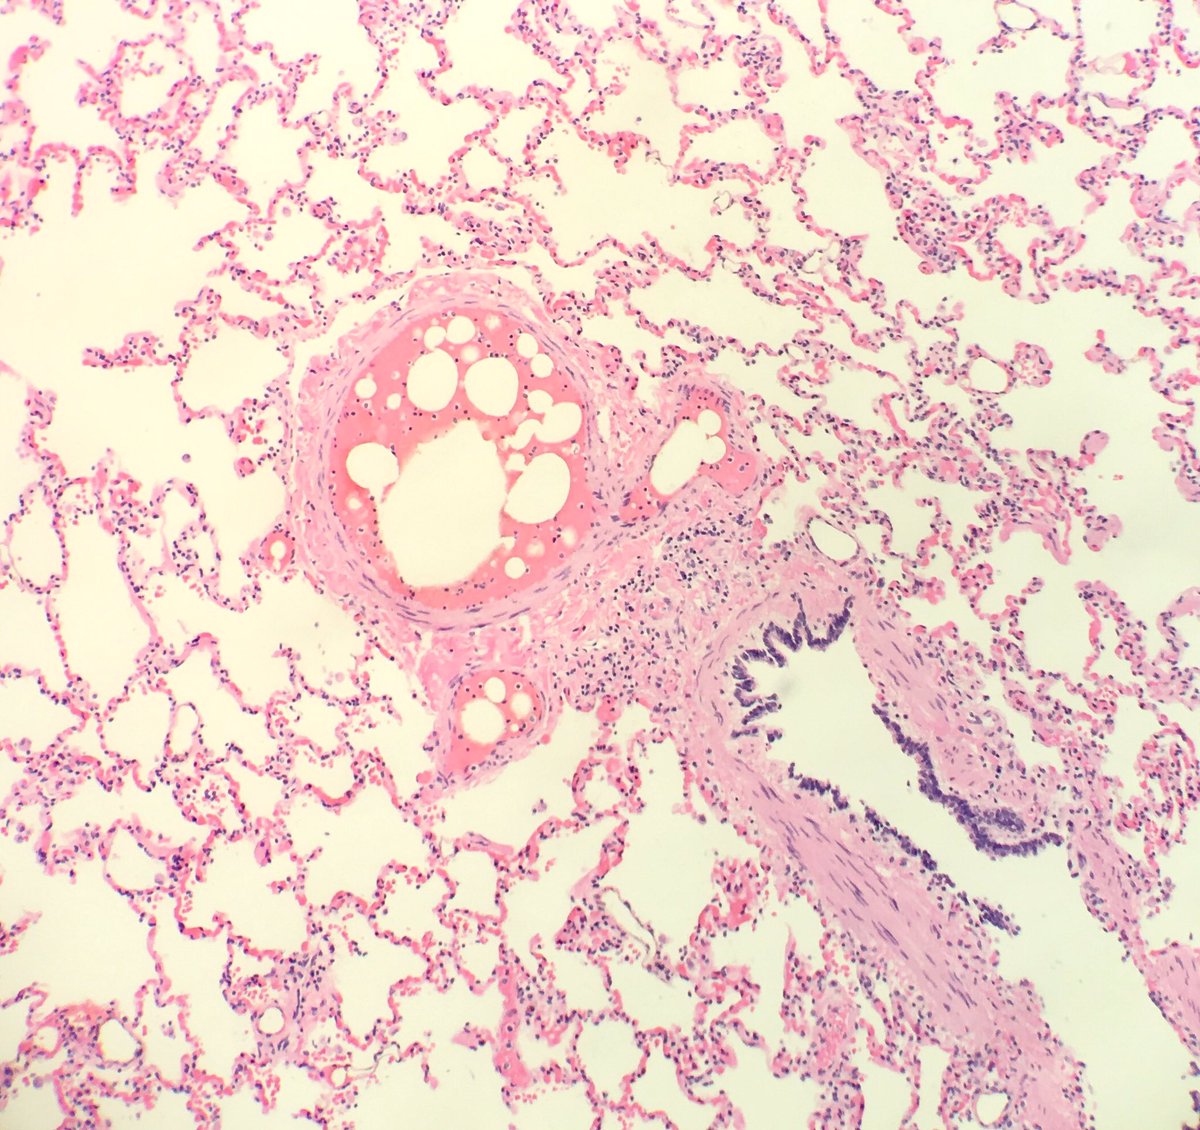

Fat emboli: ~85% of trauma patients w/ attempted resuscitation have fat emboli at autopsy. Why else? #pulmonarypath #forensicpath

seattlequinns's tweet image. Fat emboli: ~85% of trauma patients w/ attempted resuscitation have fat emboli at autopsy. Why else? #pulmonarypath #forensicpath